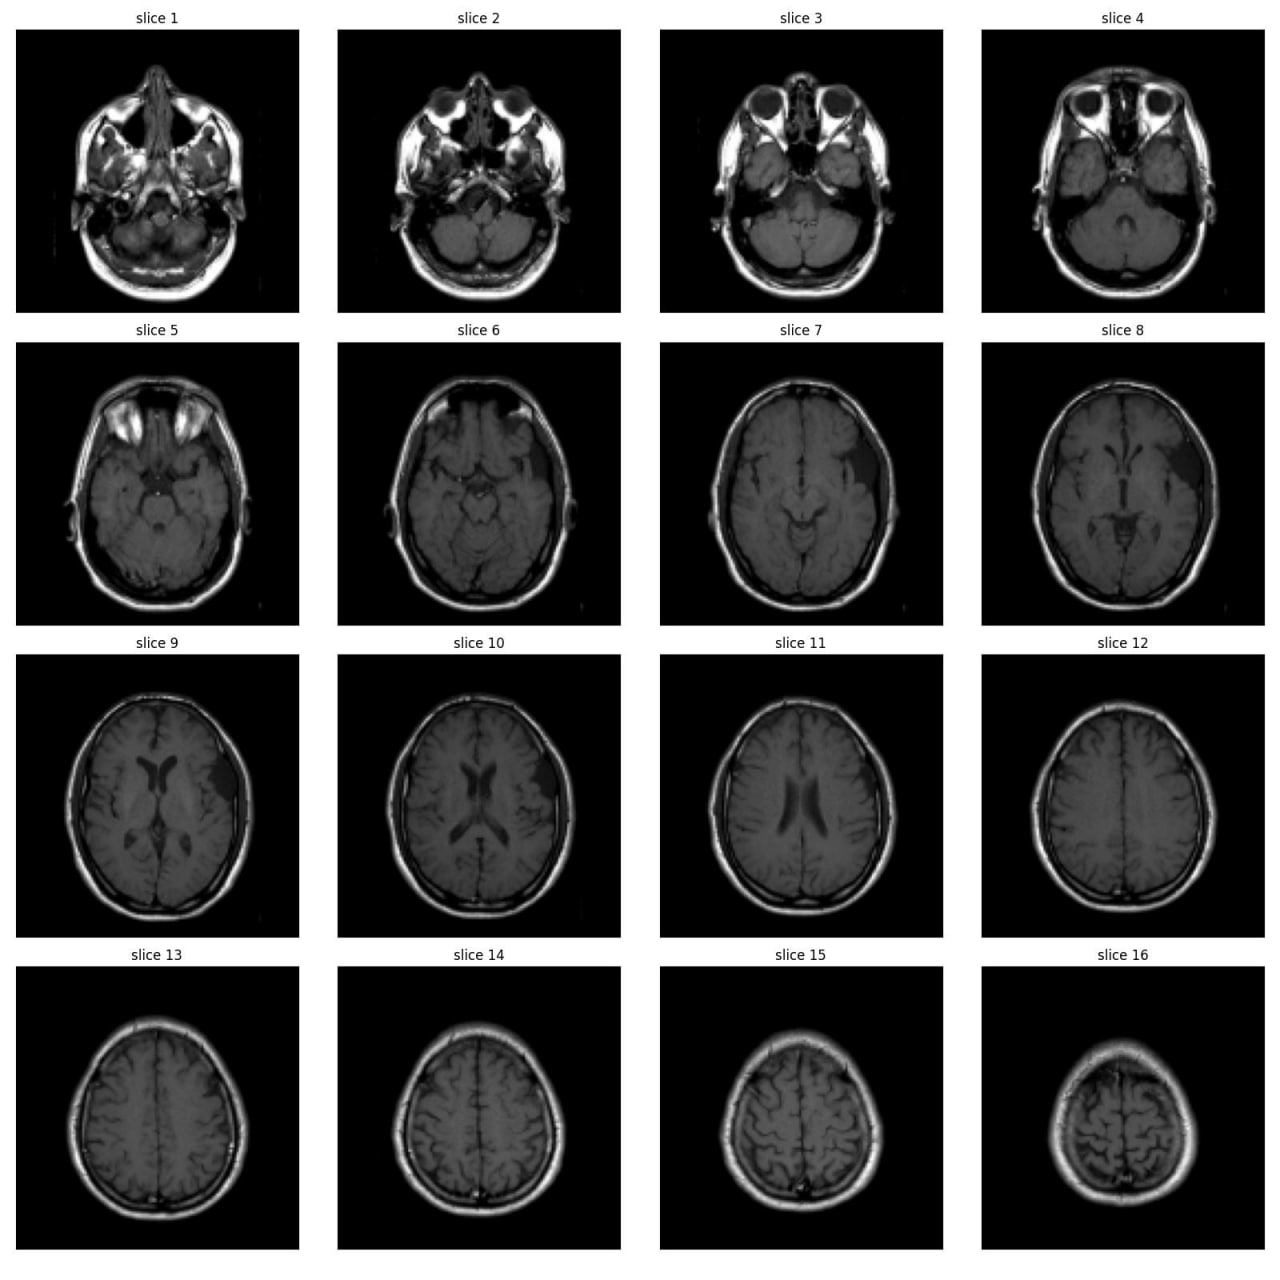

As part of the JIM3 team, I competed in the IAAA competition, which involved a dataset of 4,000 MRI images, with only 500 labeled as abnormal. The competition aimed to develop a model for patient-level abnormality classification. We utilized various models, including EfficientNet, DenseNet, ResNet, custom CNN models, and Vision Transformers (VIT), along with different preprocessing techniques. Working closely with a medical team, we converted subject-level annotations into slice-level annotations for more effective model training. Despite discovering inconsistencies in the test set and normal cases after the competition, we secured 17th place among over 100 teams. The technical team is currently working on a paper using the annotated data from this project.